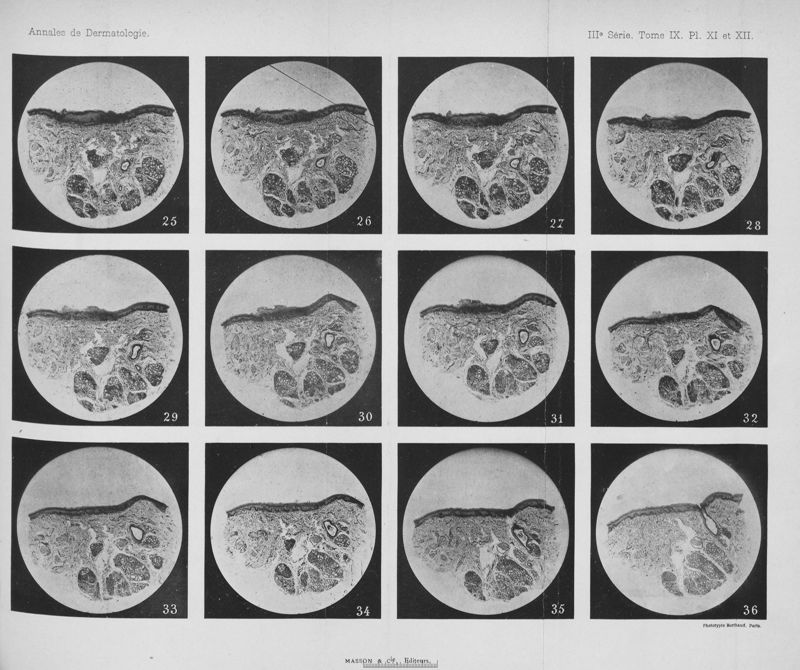

Annales de dermatologie et de syphiligraphie

3ème série, tome IX. - Paris : Masson, 1898.